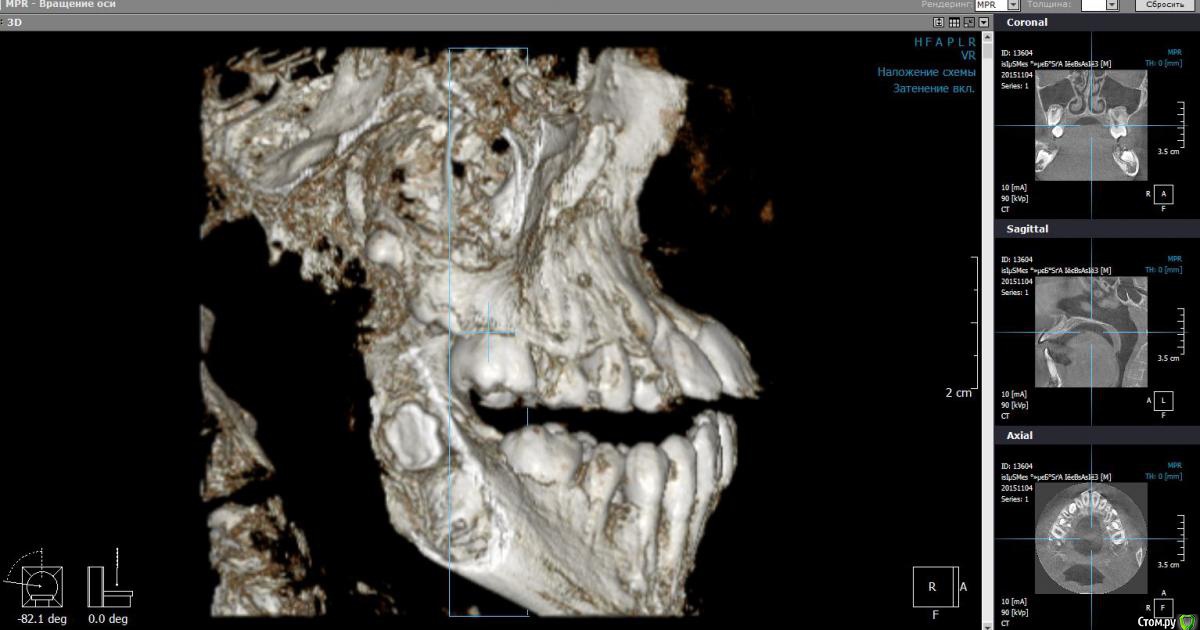

Monkey Опубликовано 27 апреля, 2016 Поделиться Опубликовано 27 апреля, 2016 (изменено) Коллеги! Прощу совета и помощи. Кто как справляется с выраженным 2-1. Парнишке 12 лет. Со слов мамы ни вредных привычек, ни родовой травмы не было. Опять же со слов мамы, есть серьезное искривление перегородки носа ( ЛОР сказал можно править только после 17 лет).Сейчас удалили зачатки 38,48. Ждем когда созреют 18,28.Как вести таких пациентов? и реально ли обойтись без хирургии? Когда начинать лечение и на каком аппарате?P.s. если у кого-то были похожие вылеченные случаи, буду благодарна за демонстрацию. Изменено 27 апреля, 2016 пользователем Monkey Ссылка на комментарий

Yana guapa Опубликовано 27 апреля, 2016 Поделиться Опубликовано 27 апреля, 2016 почему клкт делали с открытым ртом? в итоге проекции , которые вы выложили - не информативны. лучше "классика" - снимки (трг) , фото (причем полноценный набор:фас, профиль, профиль с улыбкой, обнажение резцов в покое...) это все имеет значение при составлении плана лечения и выбора методики. Ссылка на комментарий

Monkey Опубликовано 28 апреля, 2016 Автор Поделиться Опубликовано 28 апреля, 2016 почему клкт делали с открытым ртом? в итоге проекции , которые вы выложили - не информативны. лучше "классика" - снимки (трг) , фото (причем полноценный набор:фас, профиль, профиль с улыбкой, обнажение резцов в покое...) это все имеет значение при составлении плана лечения и выбора методики. Проблема в том, что ничего и нет. На консультации сказала маме, что надо ждать созревания и прорезывания зубов. но потом еще раз КТ посмотрела и решила, что надо действовать сейчас! Буду вызывать на модели и снимки. Ссылка на комментарий